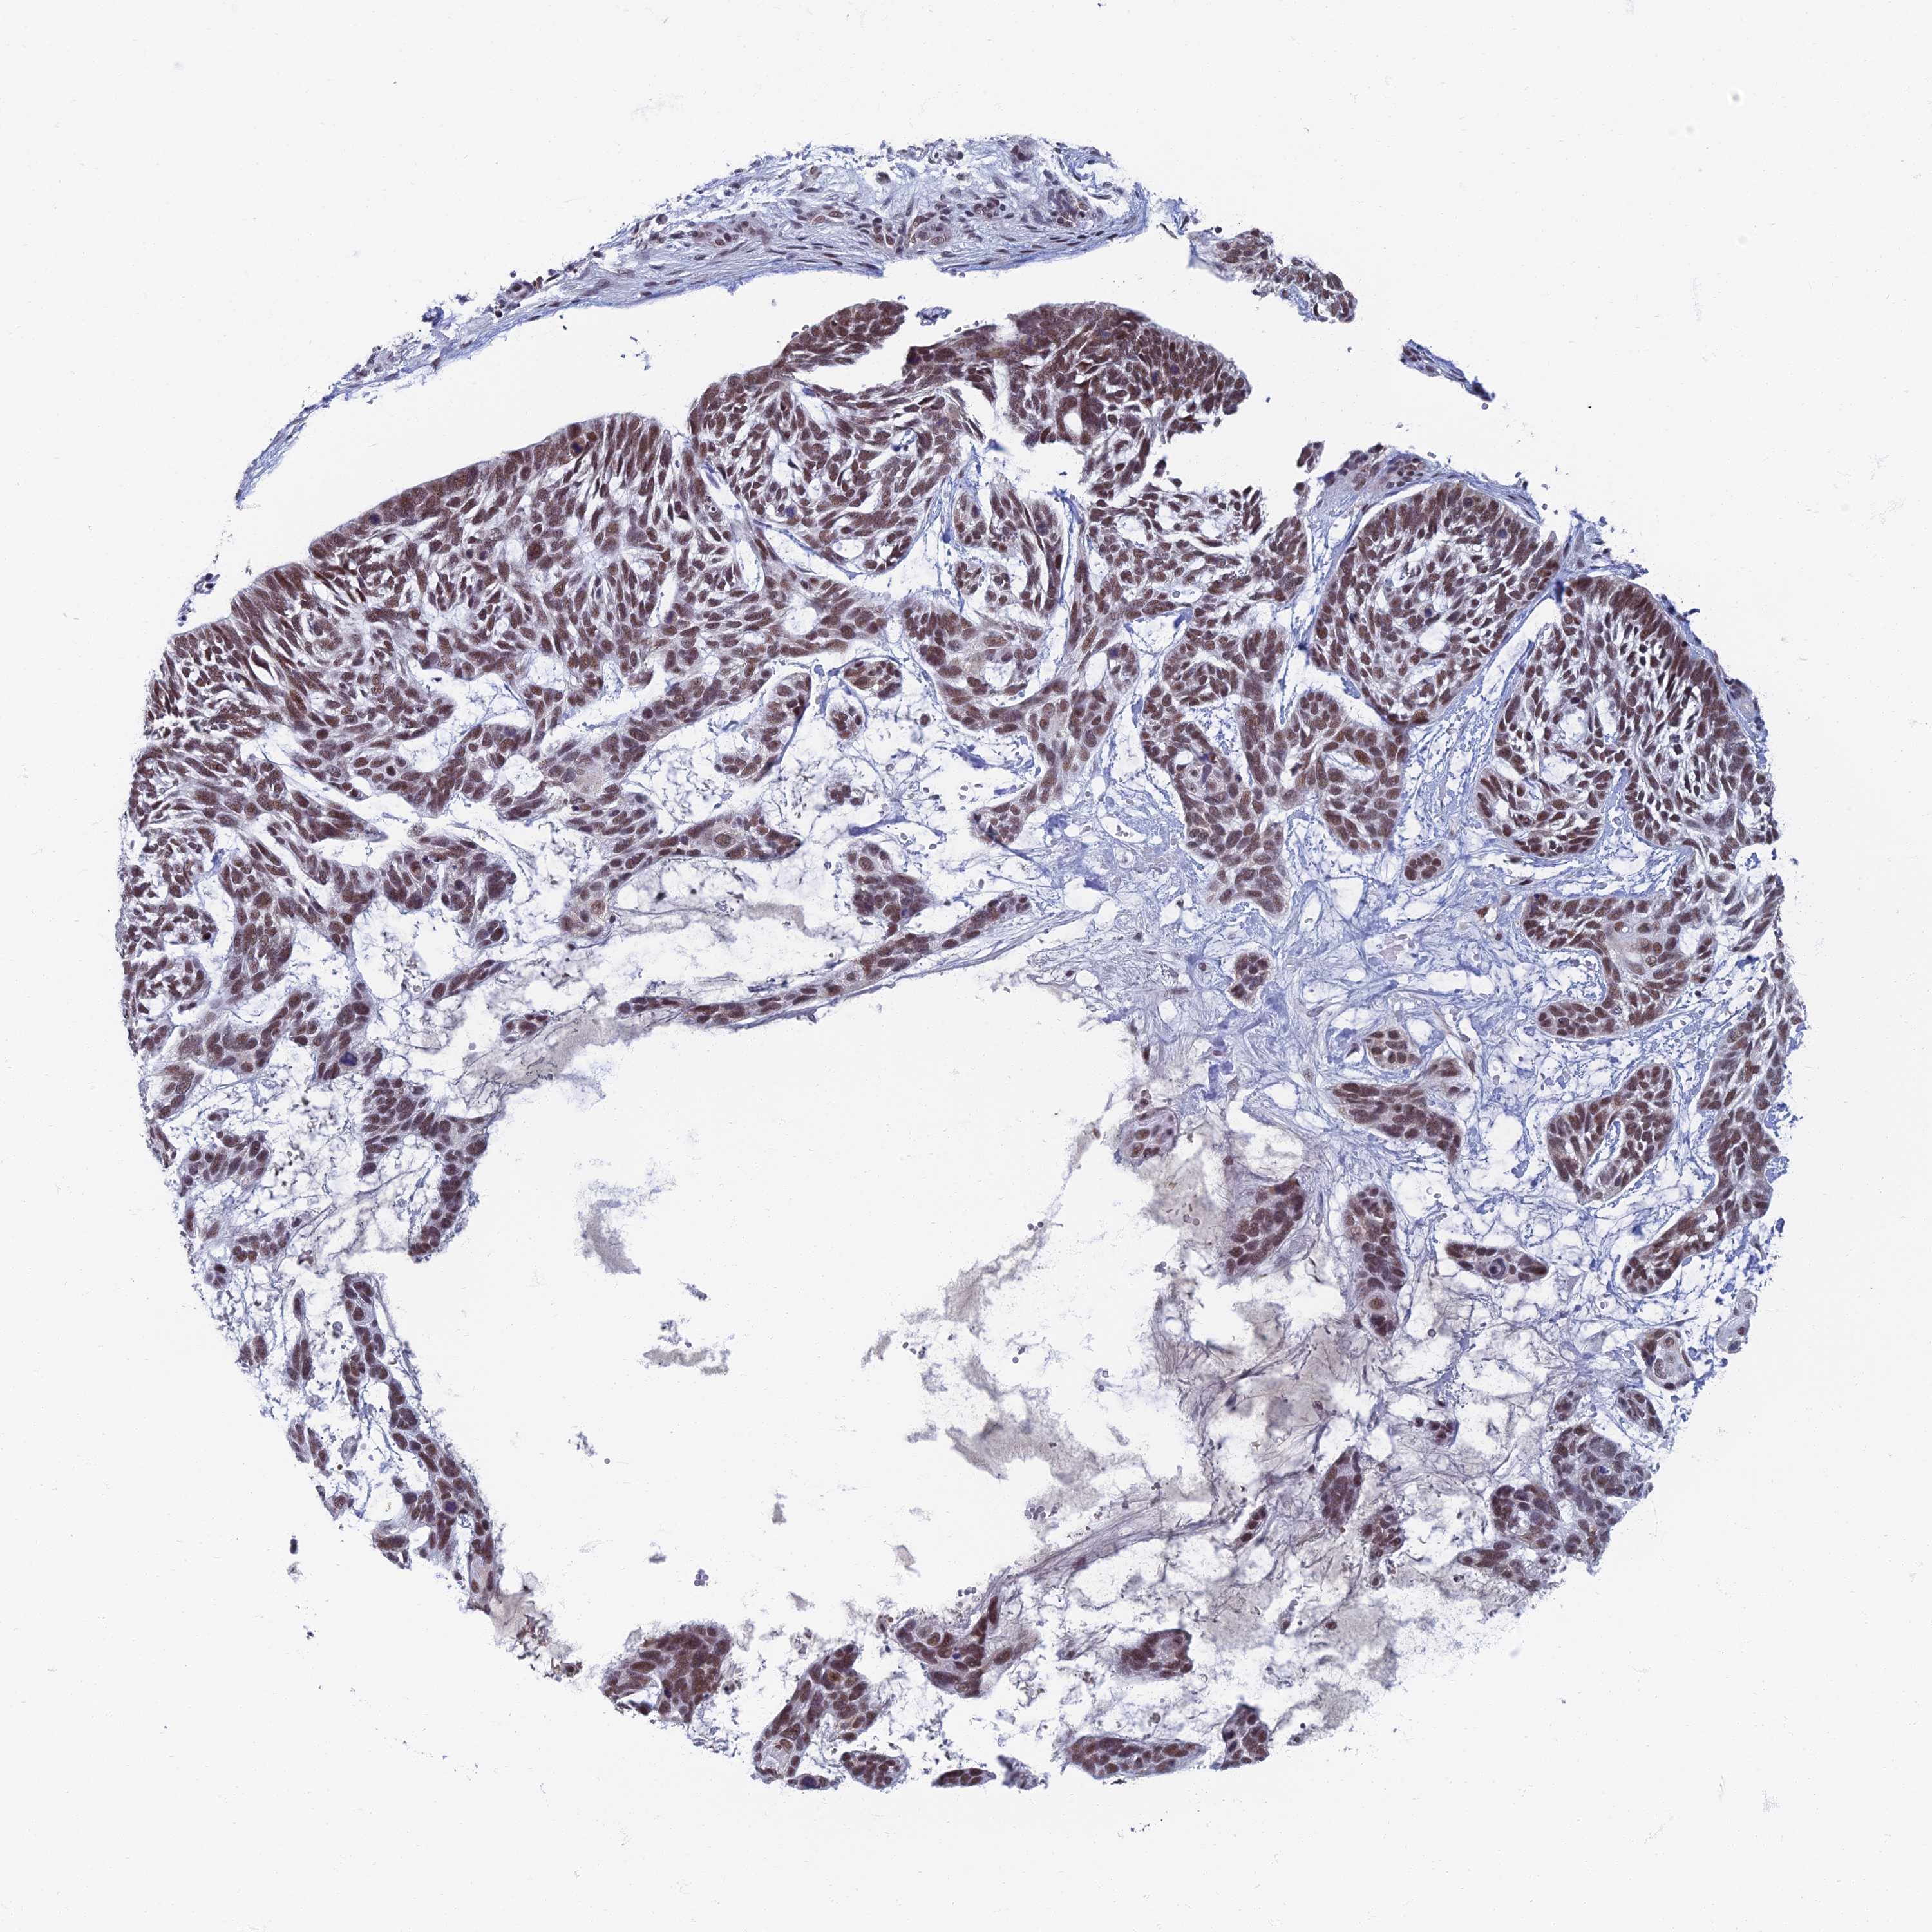

CANCER SKIN CANCER Show tissue menu

Basal cell and squamous cell cancer

SKIN CANCER - Protein expressioni

A mouse-over function shows sample information and annotation data. Click on an image to view it in a full screen mode. Samples can be filtered based on level of antibody staining by selecting one or several of the following categories: high, medium, low and not detected. The assay and annotation is described here.

Each image is clickable and will lead to virtual microscopy that enables deeper exploration of all samples and also displays staining intensity scores, fraction scores and subcellular localization as well as patient and tissue information for each sample.

Antibody HPA044492

Staining

High

Strong

>75%

Location

Nuclear

Basal cell carcinoma

Squamous cell carcinoma, NOS

Squamous cell carcinoma, metastatic, NOS